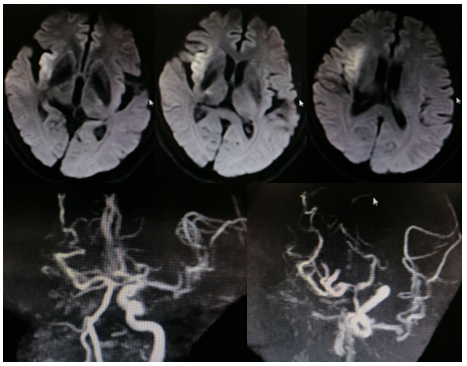

病历夹什么径技·第151期|串联营病历夹:京广连营_https://www.jmylbn.com_新闻资讯_第72张

病历夹什么径技·第151期|串联营病历夹:京广连营_https://www.jmylbn.com_新闻资讯_第73张

病历夹什么径技·第151期|串联营病历夹:京广连营_https://www.jmylbn.com_新闻资讯_第74张

<<滑动查看下一张图片>>

结论:颅脑CT提示左侧基底节、放射冠区腔隙样软化灶。颅脑DWI提示双侧小脑、桥脑、中脑、双侧海马、双侧枕叶、右侧丘脑及右侧胼胝体多发急性脑梗塞。颅脑MRA提示基底动脉及双侧大脑后动脉未见显示;右侧大脑中动脉中-重度狭窄;脑动脉硬化。初步诊断为急性后循环脑梗死,基底动脉闭塞。